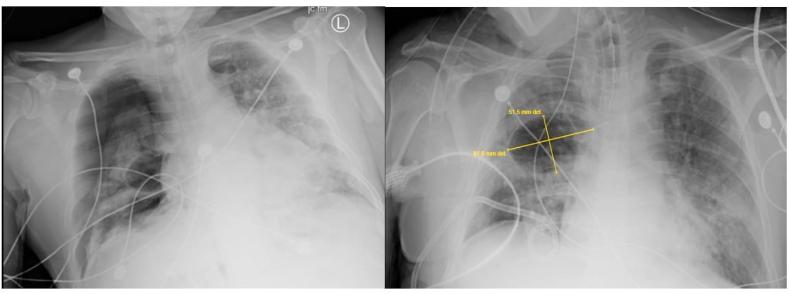

Coronavirus disease 2019 (COVID-19) has spread to more than 70 countries around the world since its discovery in 2019. More than 2.5 million cases and more than 130,000 deaths have been reported in the United States alone. The common radiological presentation in this disease is noted to be the presence of ground glass opacities and/or consolidations. We report a case of 40-year-old male admitted for COVID-19 and rapidly deteriorated into severe acute respiratory distress syndrome requiring intubation and mechanical ventilation with no prior history of smoking or lung disease. The patient had normal imaging 3 days prior to admission to the hospital and rapidly developed a large pneumatocele with pneumothorax requiring chest tube placement that later on resolved. This is a unique radiologic finding in COVID-19 and likely related to severe inflammation secondary to SARS-CoV-2 infection.

自2019年发现以来,2019冠状病毒病(COVID-19)已传播至全球70多个国家。仅在美国就报告了超过250万例病例和超过13万例死亡。该疾病常见的影像学表现为磨玻璃影和/或实变。我们报告一例40岁男性因COVID-19入院,迅速恶化为严重急性呼吸窘迫综合征,需要插管和机械通气,既往无吸烟或肺部疾病史。患者入院前3天影像学检查正常,迅速出现一个大的肺气囊并伴有气胸,需要放置胸管,随后气胸消散。这是COVID-19中一种独特的影像学表现,可能与严重急性呼吸综合征冠状病毒2(SARS-CoV-2)感染继发的严重炎症有关。